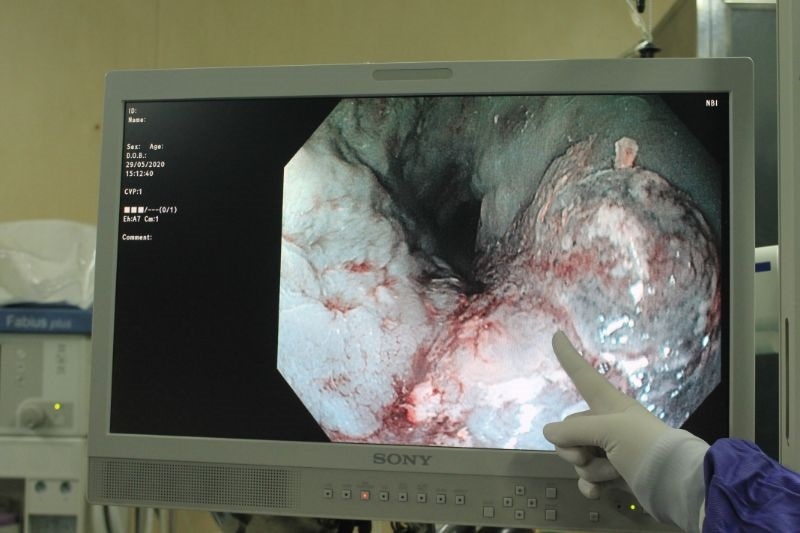

Trong quá trình thực hiện, các bác sĩ dùng kỹ thuật chẩn đoán ung thư sớm và đã phát hiện bệnh nhân bị ung thư thực quản. Ảnh: Thanh Xuân.

Khá bất ngờ, các bác sĩ phát hiện thấy đó là một tổn thương sùi, đoạn thực quản nhiễm cứng chiếm 1/2 chu vi, dài khoản 2-3 cm…

Các bác sĩ tiến hành nhuộm màu NBI (chẩn đoán ung thư sớm) và nghĩ đến việc bệnh nhân bị ung thư thực quản. Các bác sĩ đã lấy mẫu bệnh phẩm để sinh tiết tìm tế bào ung thư cho bệnh nhân.